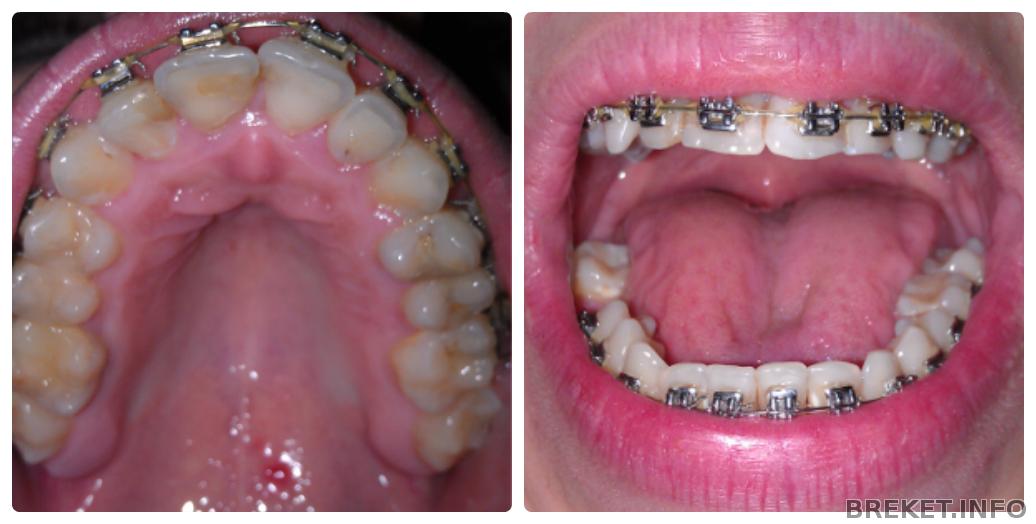

Зуб находится в десне так что не знаю как его будут вытаскивать. Боюсь он сможет задеть рядом стоящий зуб. Хотя хирург говорил что легко сможет.

Снимок был сделан летом. И ситуация немного изменилась, промежуток немного затянулся.